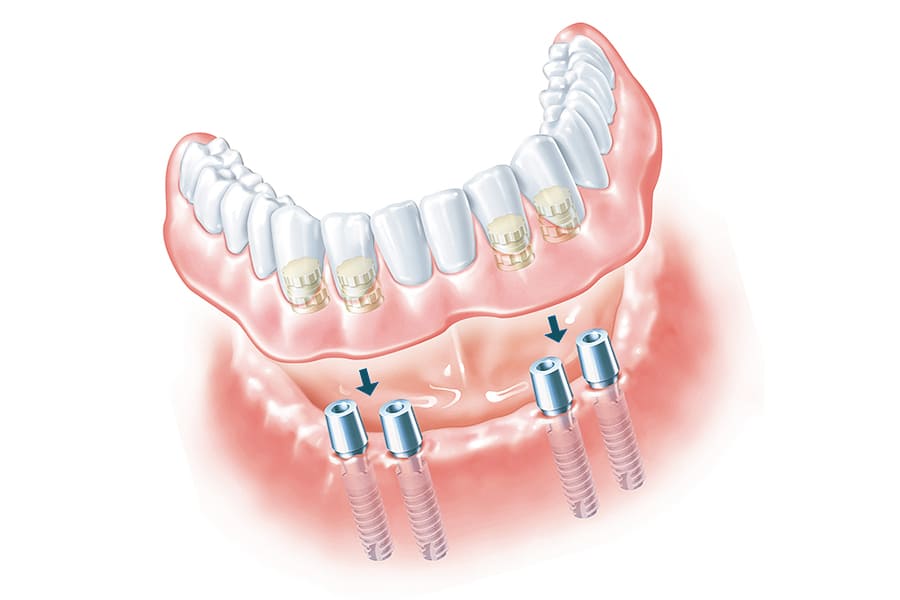

Современные съемные протезы на локаторах: Фото и примеры